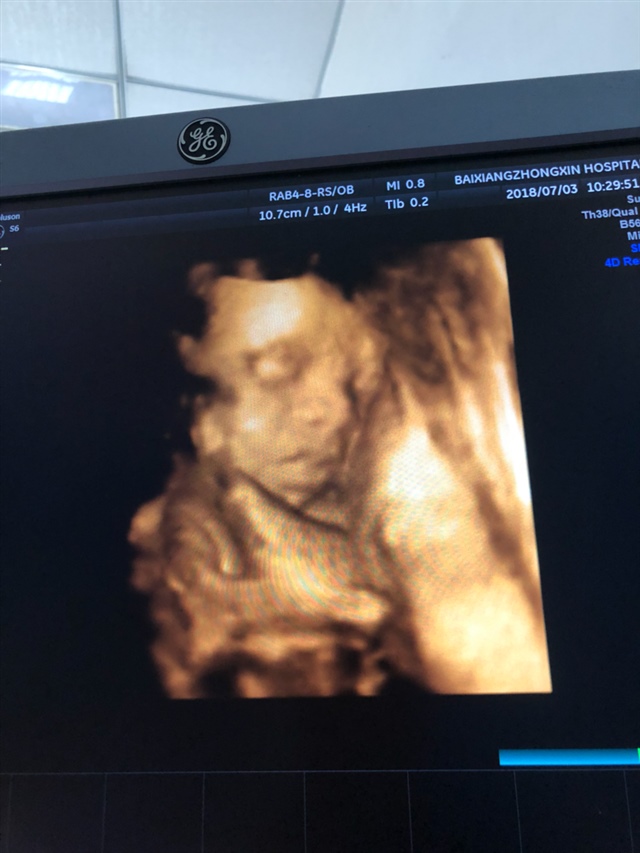

孕21周+0天

接四维顺利通过